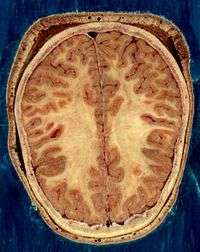

- ↑ From the National Library of Medicine's Visible Human Project. In this project, two human cadavers (from a man and a woman) were frozen and then sliced into thin sections, which were individually photographed and digitized. The slice here is taken from a small distance below the top of the brain, and shows the cerebral cortex (the convoluted cellular layer on the outside) and the underlying white matter, which consists of myelinated fiber tracts traveling to and from the cerebral cortex.